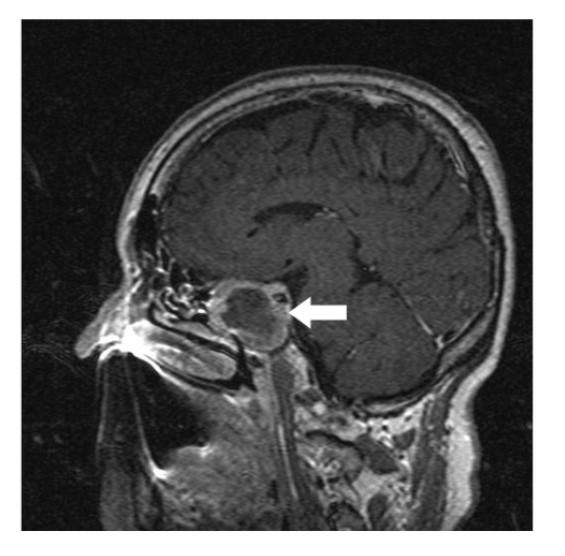

A 64-year-old lady presented to the outpatient department with complaints of headache and right eye blurring of vision for one month. Neurological examination revealed that bitemporal hemianopsia and impairment of visual acuity. Findings from fundus examination were within normal limits. Rest of the brain appeared unremarkable. Endocrine evaluation was normal. Results of renal function tests, liver function tests and haemogram test were within normal limits. A clinical diagnosis of non-secretory pituitary adenoma was made. Magnetic resonance imaging showed a well-circumscribed contrast-enhancing lesion in the sella (Figure 1, Figure 2). The patient underwent an endoscopic endonasal/transsfenoidal surgery in the supine position and total lesion resection was peformed. Intraoperatively, the lesion was found to be yellow colour, soft and avascular and it was removed totally until the sella turcica was visualized (Figure 3).In histopathologic examination septate hyphae were observed between inflammatory cells, Grocott staining is positive, but acid-fast stain for acid-fast bacilli (AFB) was negative. Histopathological findings suggest that infection of Actinomyces (Figure 4, Figure 5). We performed to patient consulted by patients to infectious diseases clinic. Patients underwent intravenous 6x2 gr ampicillin for four weeks.Then oral 4X500 mg amoxicillin treatment is planned a for at least 6 months. Patient did not have any deficits in the next six months.

Figure 1.White arrow shows on sagittal section of MRI that a well-circumscribed contrast-enhancing lesion in the sella

White arrow shows on sagittal section of MRI that a well-circumscribed contrast-enhancing lesion in the sella

Preoperative diagnosis of pituitary abcess is difficult because the presenting symptoms in these patients are similar to that in patients with pituitary adenomas 4. The most common symptoms are headache, vision disturbances and endocrinological abnormalities 5. Magnetic resonance imaging is the best imaging modality for sellar abscess and the features include a hypo- or iso-intense sellar mass on T1-weighted sequences and a hypointense mass on T2-weighted sequences pituitary abscesses may be divided into primary and secondary types. Primary pituitary abscesses occur within a previously healthy gland, while secondary abscesses arise within an existing lesion, such as an adenoma, craniopharyngioma, or Rathke's cleft cyst. Secondary abscesses share radiologic characteristics with the lesions from which they arise. The typical primary pituitary abscess gives the same or slightly lower signal than brain on T1-weighted images, and could be mistaken for a solid mass or presumed to represent a pituitary adenoma. Contrast-enhanced images are useful, demonstrating absence of central enhancement, suggesting a fluid or necrotic center 6.Actinomyces brain abscess is usually diagnosed based on the contrast enhancement on the periphery as in this case.Also MRI spectroscopy findings are the described in actinomyces infection 7, 8.